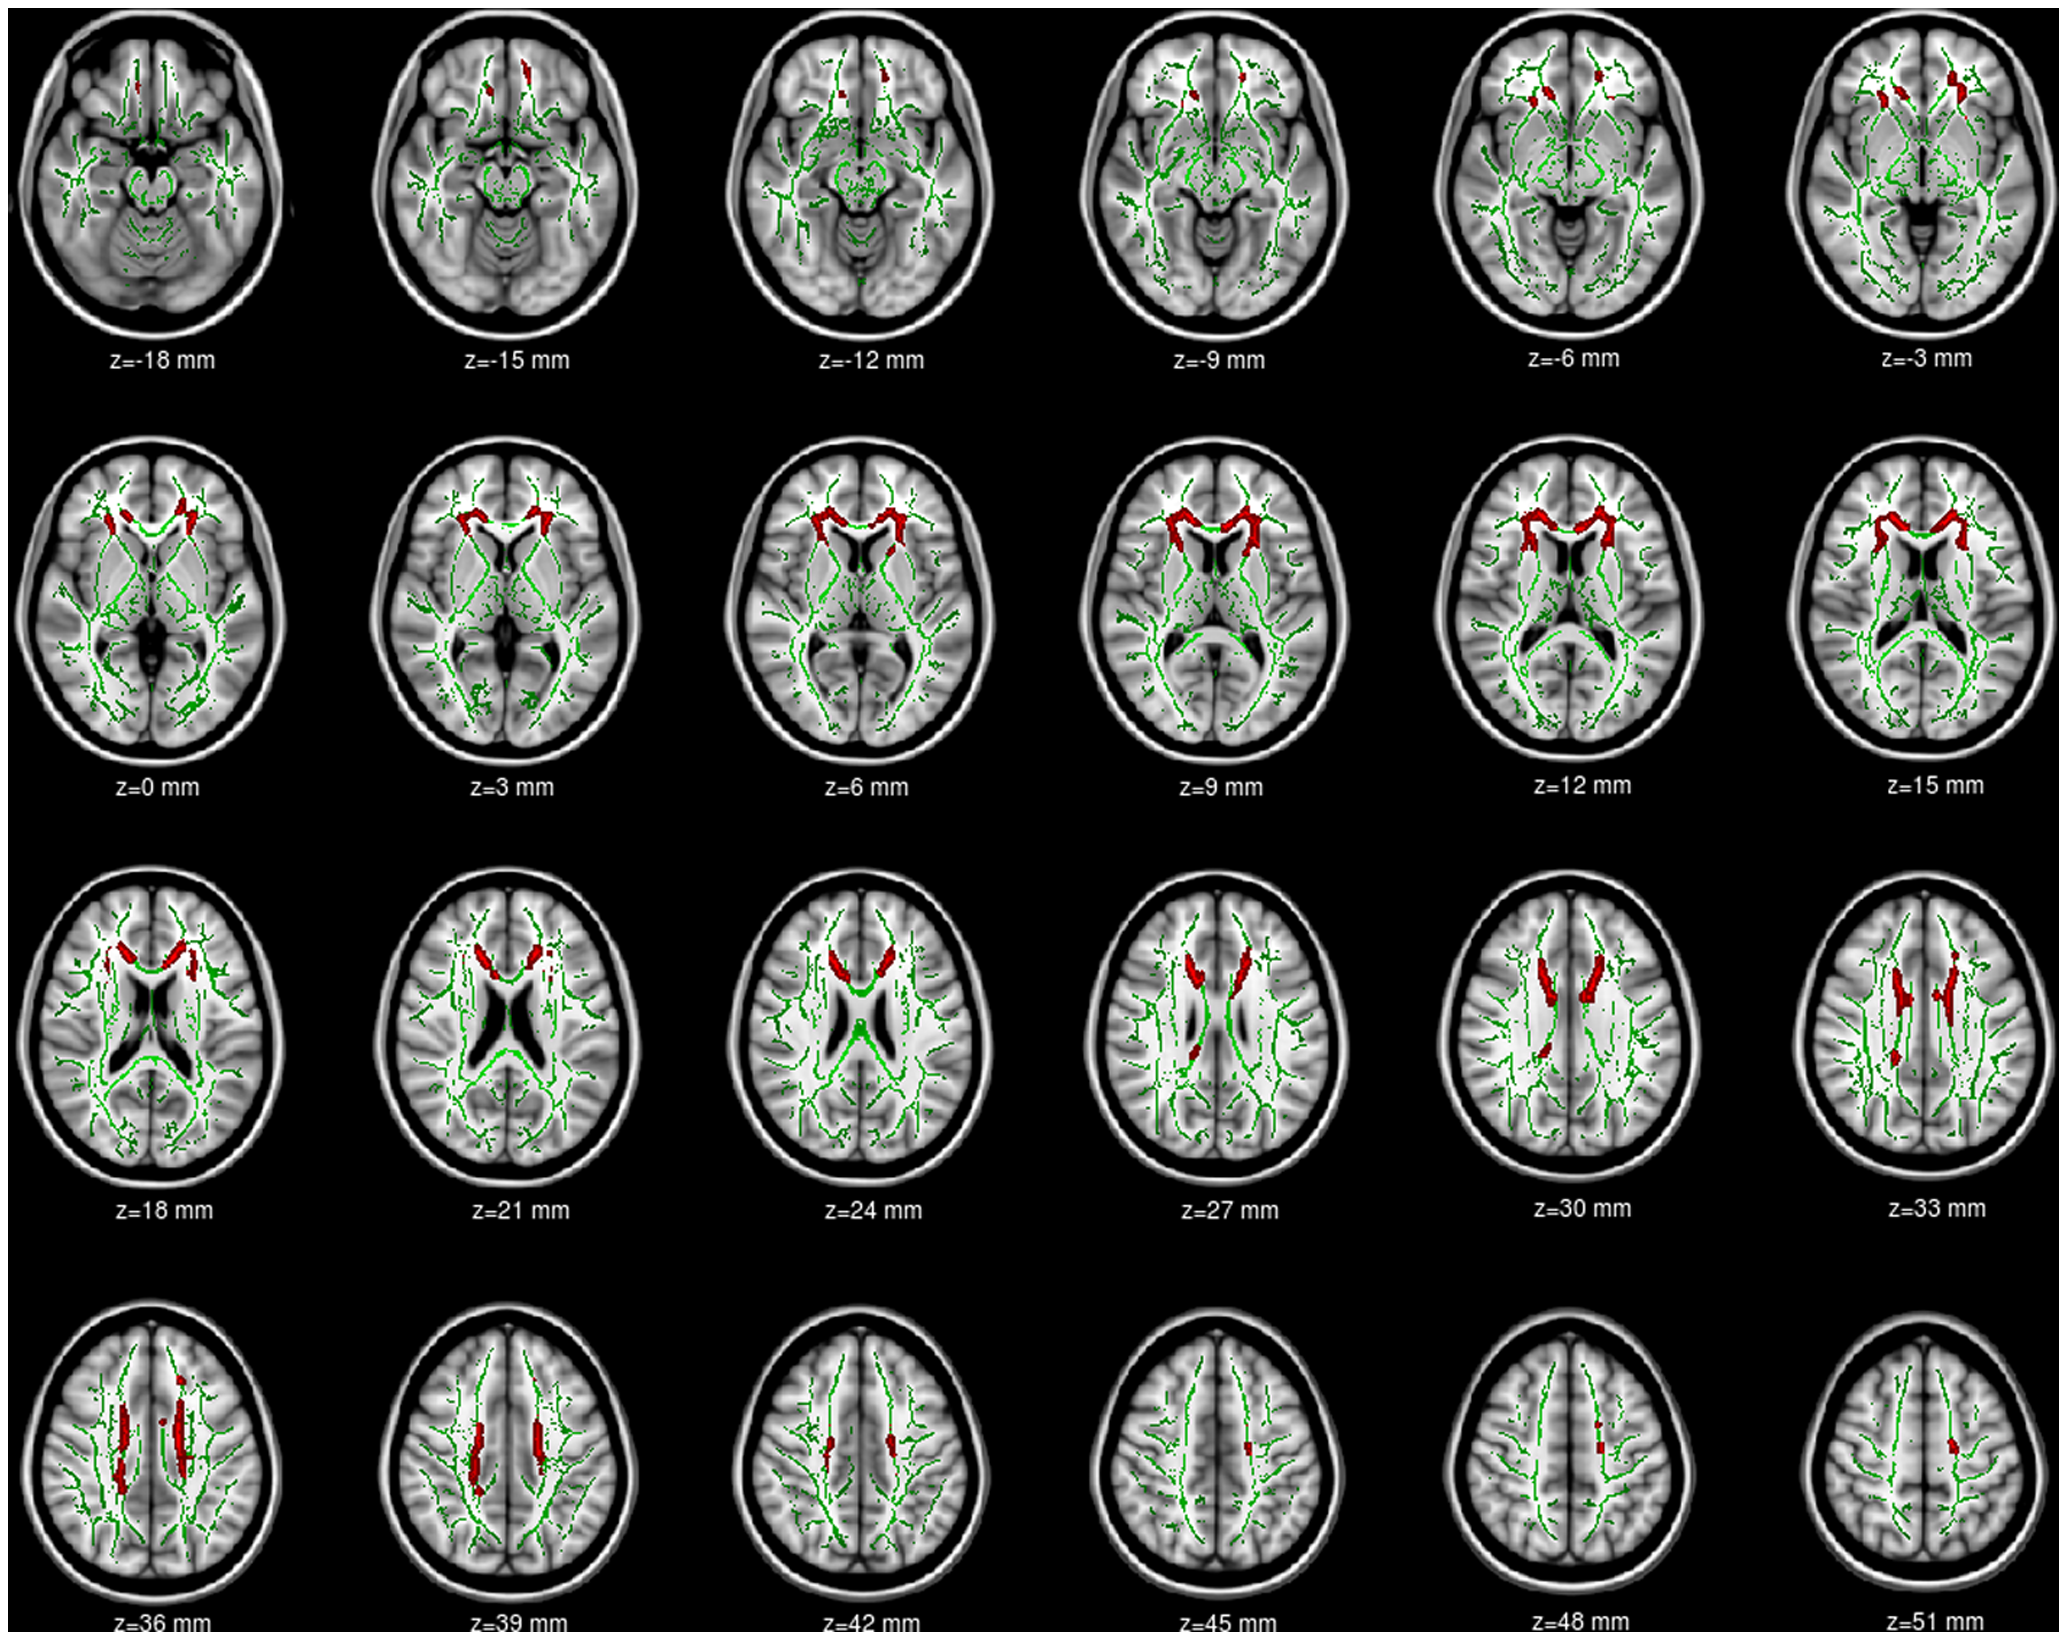

Например, китайские учёные в 2012 году опубликовали визуализацию различных регионов мозга у людей с IAD. Это ограниченное исследование, в котором приняли участие всего 17 пациентов:

Отличия в отдельных регионах мозга у этих людей по сравнению со здоровой контрольной группой:

Красным цветом выделены области, в которых функциональная активность значительно ниже (p<0,01, с поправкой на TFCE) у подростков с IAD по сравнению с контрольными группами без IAD. Левая часть изображения соответствует правому полушарию мозга

Нейроанатомические области с пониженной функциональной активностью у подростков с расстройством интернет-зависимости по сравнению с контрольной группой (p<0,01, с поправкой на TFCE)